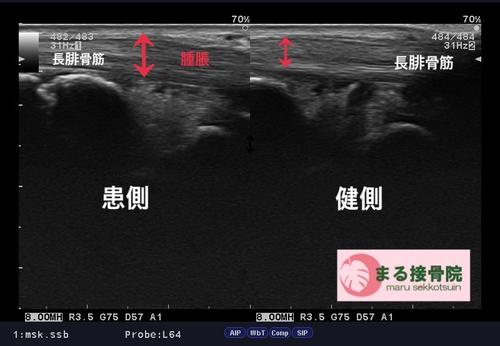

長腓骨筋腱炎 エコー.JPG

治療法としては、なによりも腫れの除去。

そして原因となっている要因の改善・予防でございます。